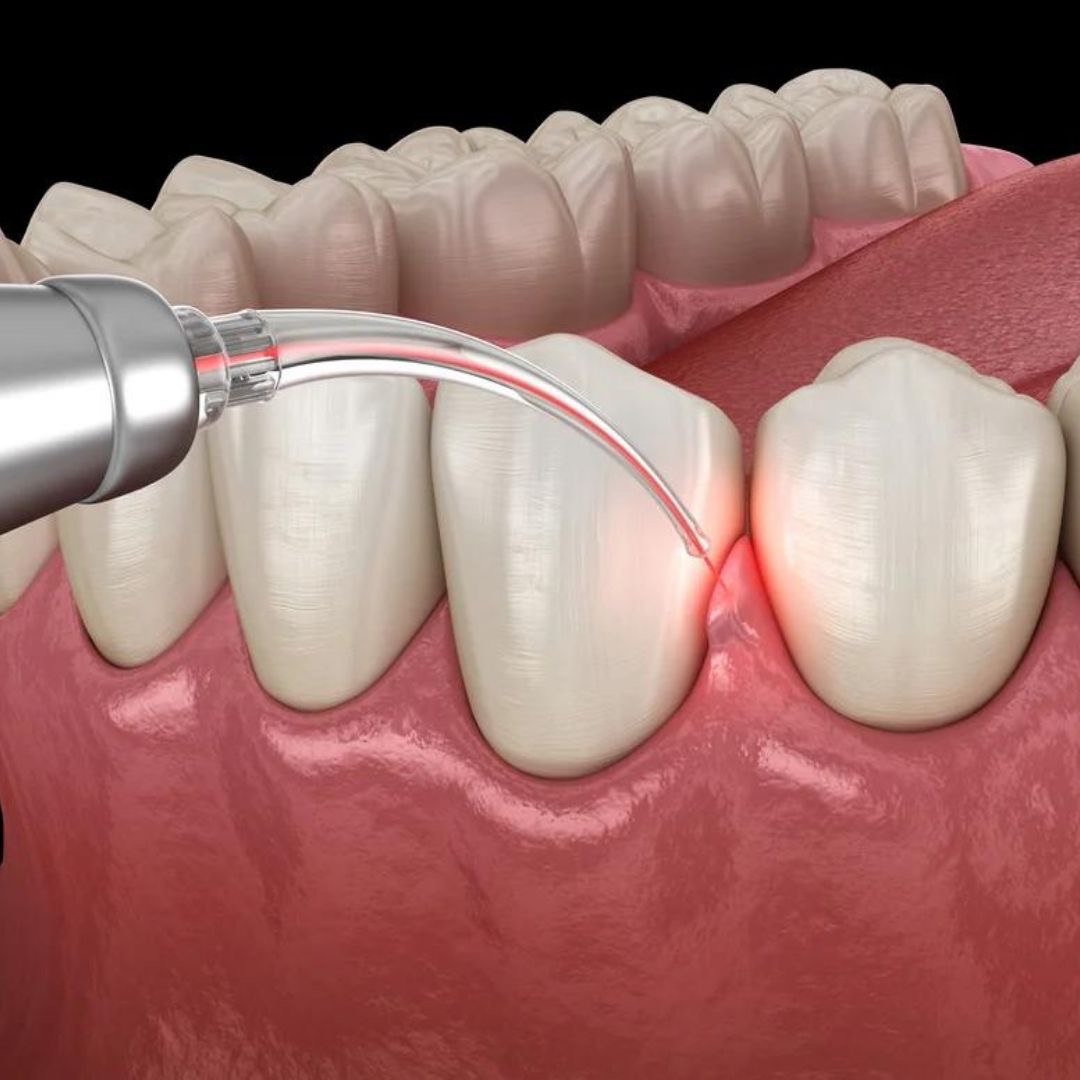

Our Treatments

Oral Surgery

Preventive & Restorative Dentistry